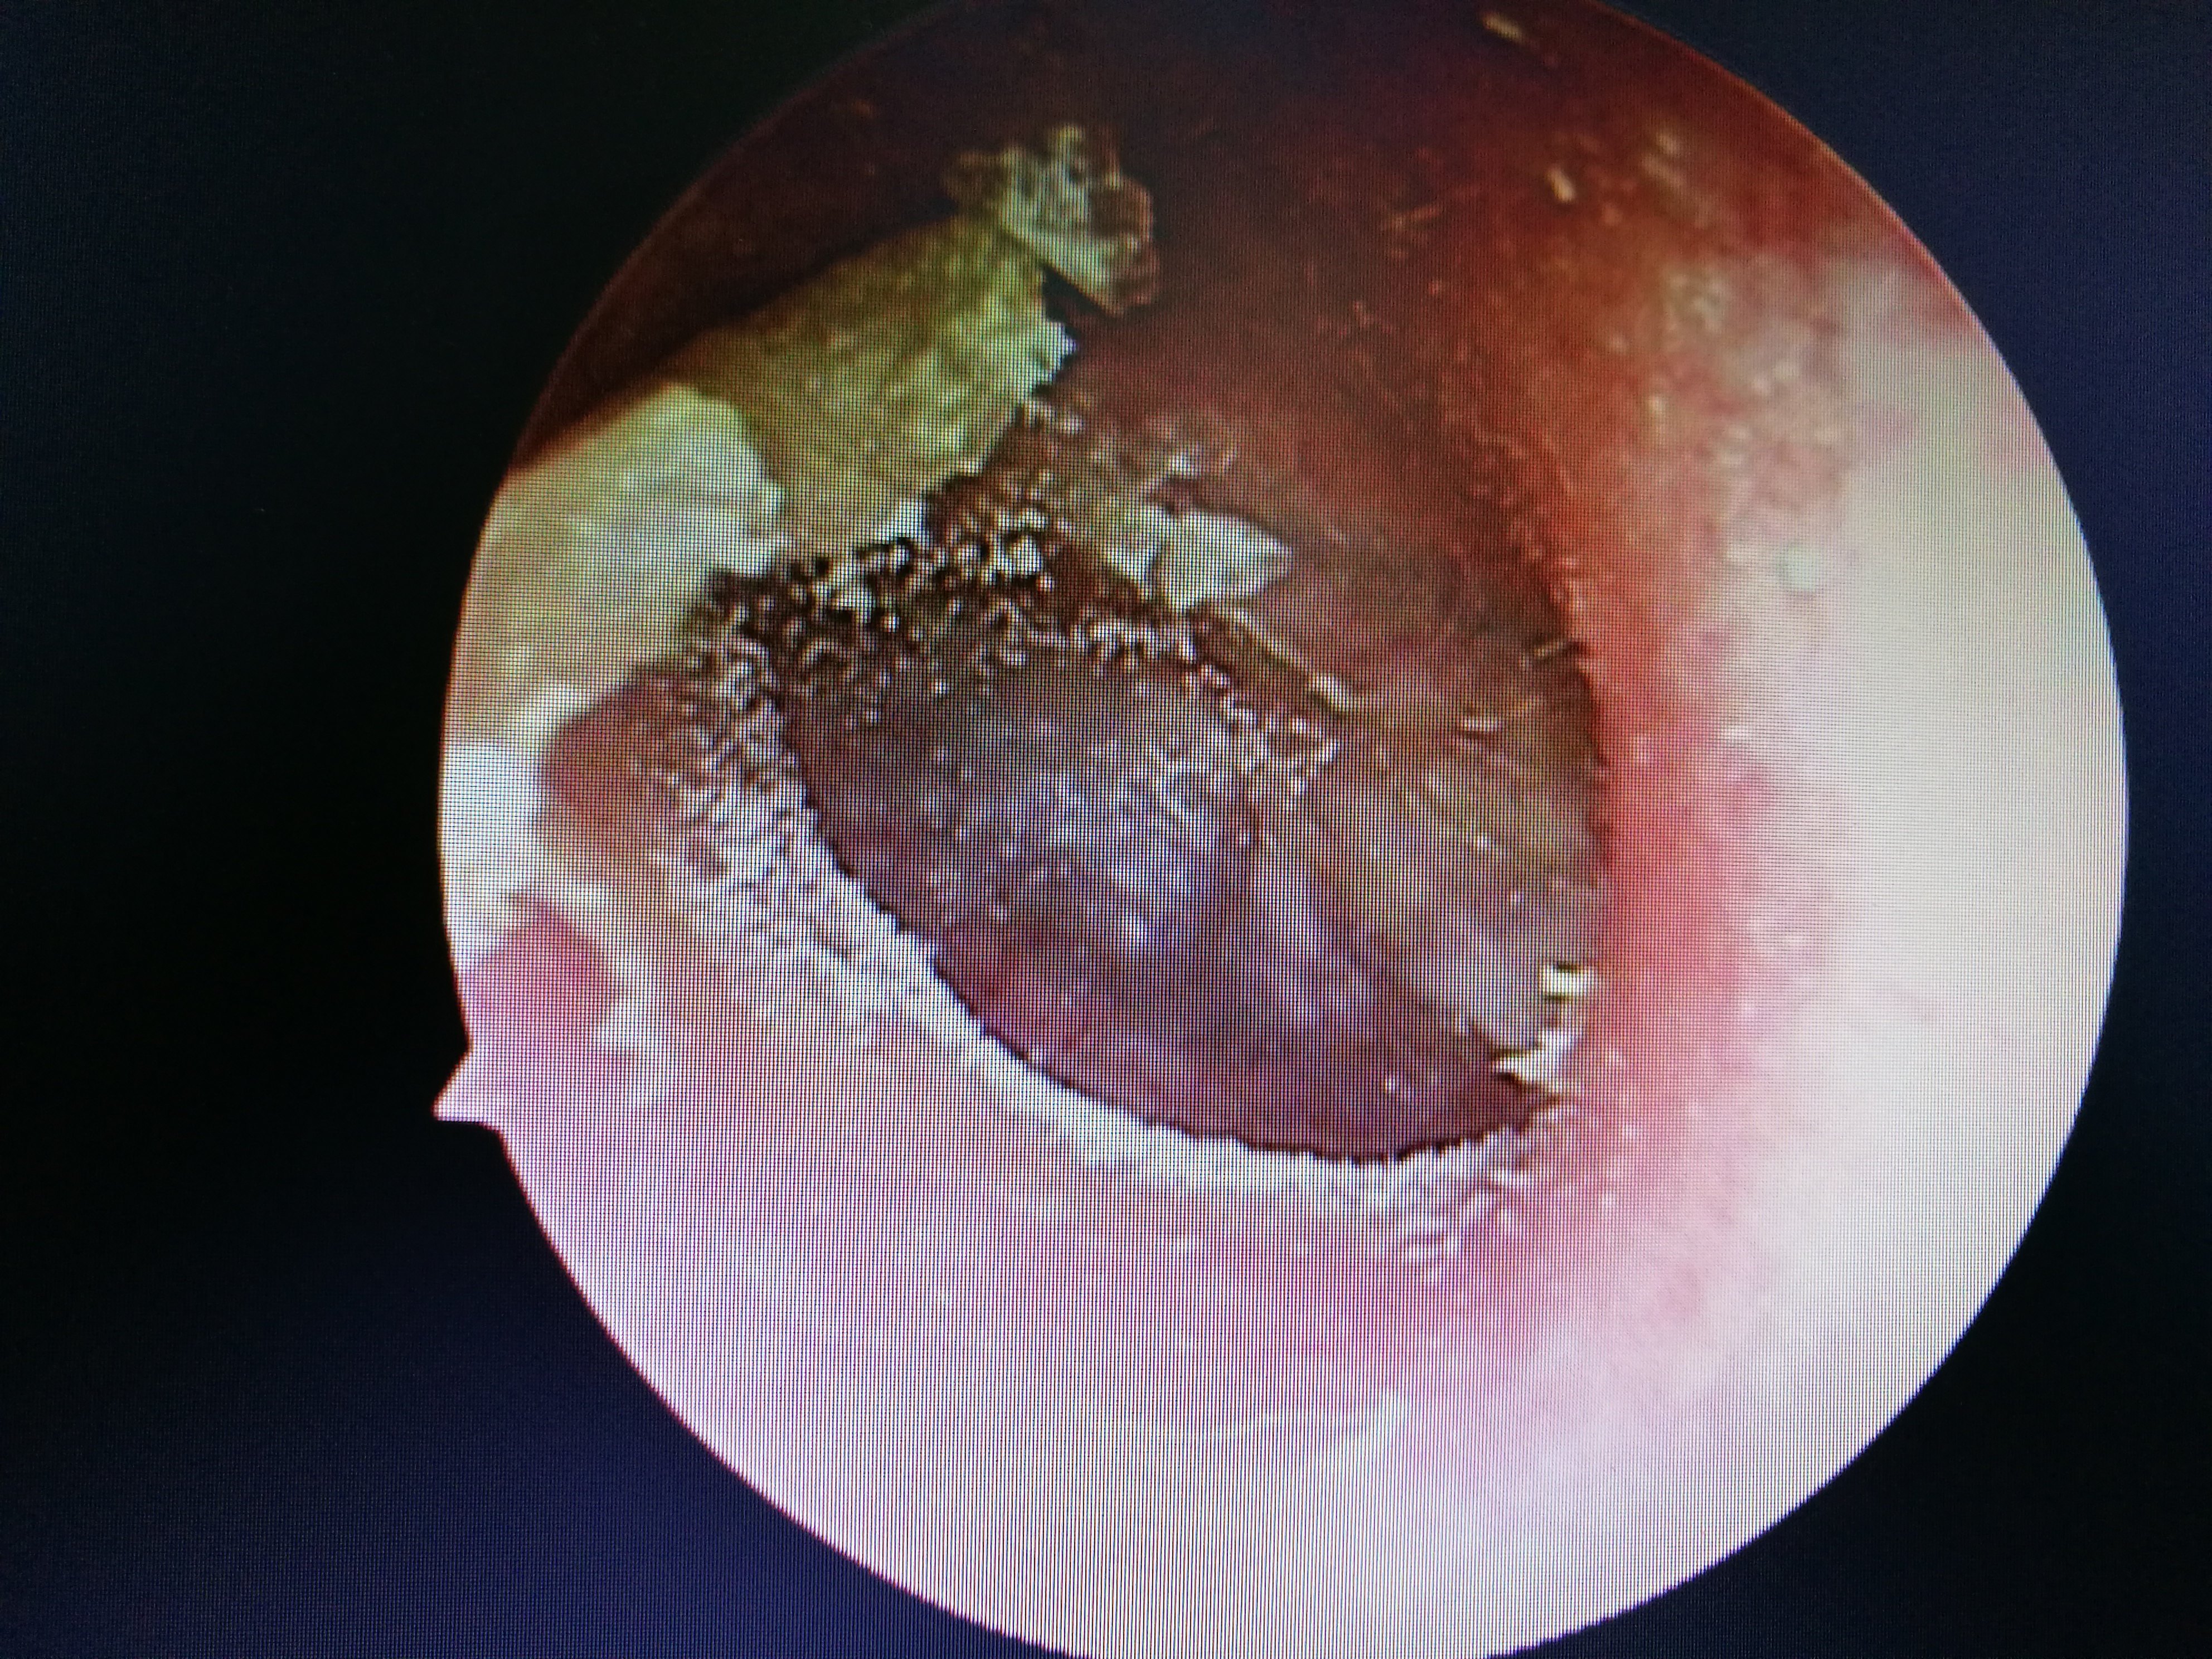

External auditory canal fungus infection, moldy ear wax blocks the ear completely耳朵也会"发霉" "我的耳朵痒死了! 整晚都没睡好,快帮我治治吧! " 通过鼻内镜检查,发现患者外耳道内都是霉菌样物,被诊断为外耳道真菌病。 外耳道真菌病是外耳道皮肤的亚急性或慢性炎性疾病,多数认为是由真菌感染所致,常合并细菌感染。 此病好发于高温、潮湿的季节,且常见于热带或亚热带地区,如我国长江及珠江流域。 引发外耳道真菌病的病菌耳朵一直响个不停听力下降怎么办 问答 网: 听力下降,不应该因为生气而引起的,还是要注意一下器质性的原因,你最好是做一下电测听 耳朵响个不停,听力也下降了,到底该怎么办?

「医生,我的耳朵好痒,感觉和人讲话隔了一层膜,听话也听不太清了!整晚都没睡好,您快帮我看看吧!」7 月 8 日,30 岁的小田(化名)到宜昌市第一人民医院耳鼻喉科就诊,经耳内镜检查发现,他的右侧耳道充 中国宁波网记者 陈敏 通讯员 陆达锴 郭豪伦 长期掏耳朵,竟导致耳道内长满了霉花,甚至影响了听力。说起自己的这个怪病,家住海曙区的张先生男子采耳后患上"脚气病"?医生透露原因 采耳后,耳朵为何会患上"脚气病"? 主治医师高险亭表示,这些患者基本都是因为耳朵痒、耳朵不舒服来就诊,检查结果显示耳朵已经发霉,满是霉菌,患上真菌

医生告诉记者,在洗头店、洗浴中心等处的非专业采耳,是真菌性外耳道炎感染途径之一,如果挖耳勺没有清洁干净,在掏耳朵的时候又不小心弄伤了脆弱的外耳道皮肤,就很容易引起病菌感染。 "而且平时在洗浴之后耳道进水,潮湿的耳道也给真菌提供了绝佳的生长温床,进而感染上了真菌性外耳道炎。 "医生说。 另外,朱先生在平时耳朵或其他身体不适时习惯性 医生说,这是耳朵里面发霉了!原来这是一种典型的外耳道疾病:霉菌性外耳道炎,又叫外耳道真菌病,它是一种外耳道的真菌感染性疾病,临床并不少见。 霉菌性外耳道炎是由霉菌感染所引起的,属于机会感染。 致病原因主要有 1、机体免疫缺陷或抵抗力下降;